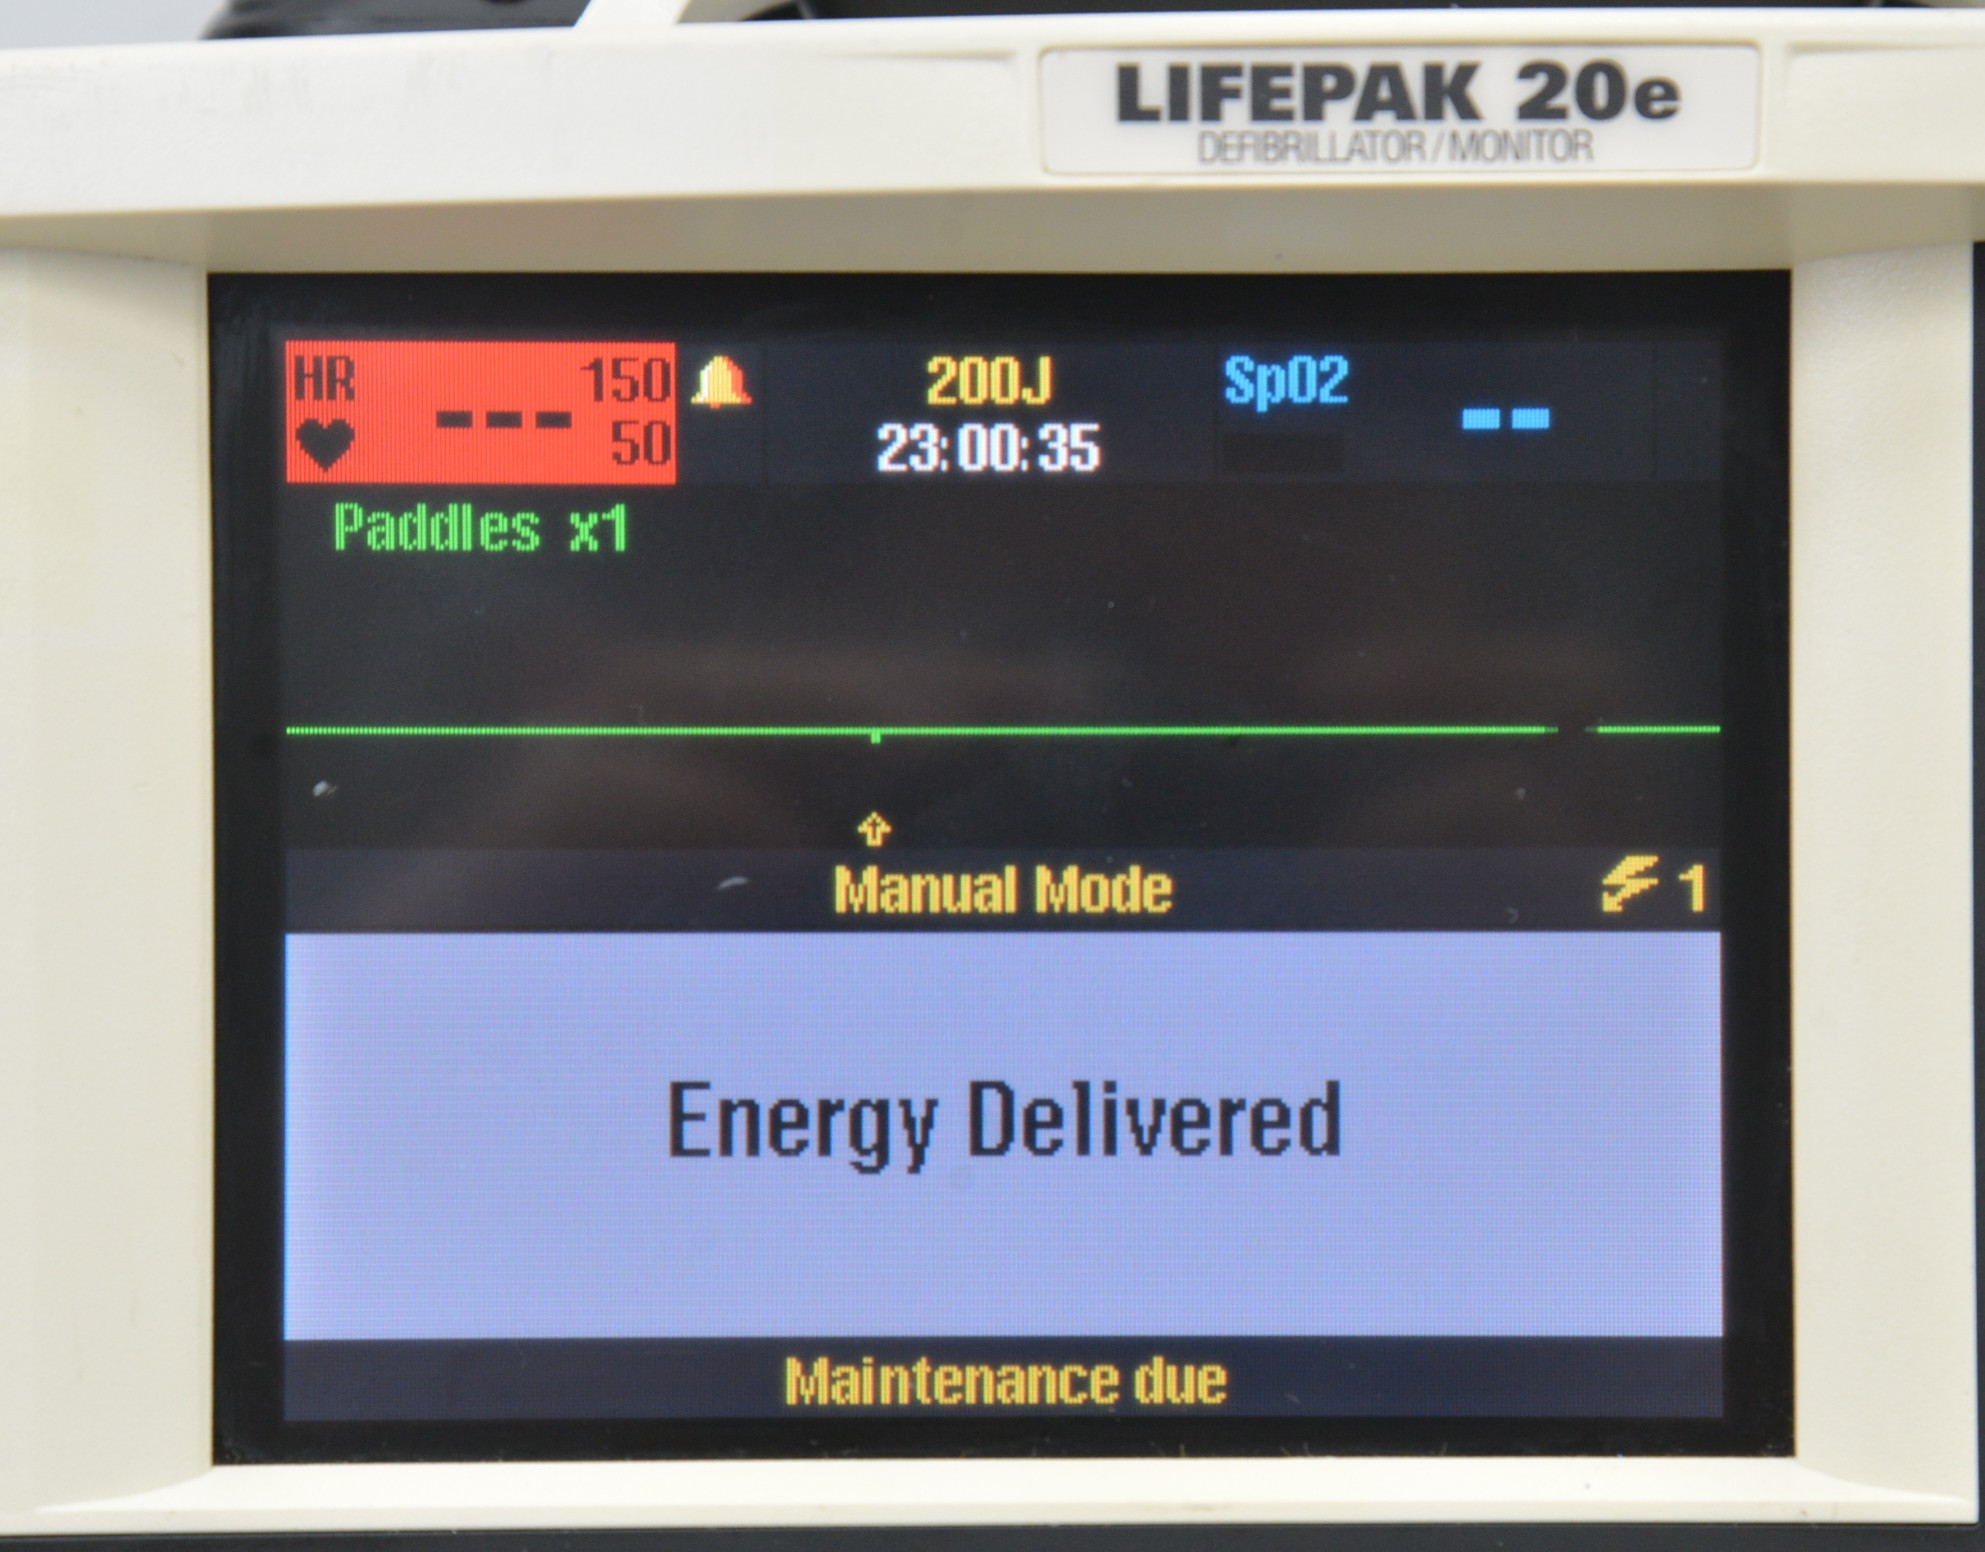

- Medtronic Lifepak 20e Defibrillator Monitor 2010 W/ Paddles

February 27, 2026Medtronic Lifepak 20e Defibrillator Monitor 2010 W/ Paddles

1 in stock

This Medtronic Lifepak 20e Defibrillator Monitor 2010 W/ Paddles is in good working condition. The unit powers on properly and responds to selections. All connection points are clean and in good condition. There are some scuff marks from previous use (see photos). This unit comes with a 30 day satisfaction guarantee. Includes everything in the pictures and nothing else.